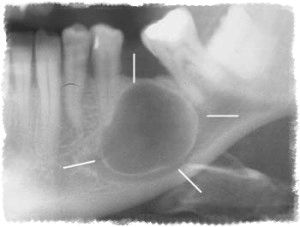

Зовні кіста виглядає як порожнину овальної або каплевидної форми, покритої щільною оболонкою. Внутрішній вміст цього новоутворення - гнійна рідина жовтуватого відтінку.

Зовнішній шар кісти обмежений клітинами сполучної тканини. Сама ж порожнину вистелена плоским багатошаровим епітелієм. Розміри варіюються від декількох міліметрів до двох сантиметрів.

Згодом в районі проекції кореня зуба можна виявити наявність невеликого горбка, розміри якого збільшуються в міру розвитку захворювання.